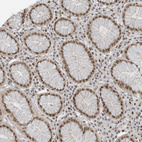

Immunohistochemical staining of human stomach shows moderate to strong nuclear positivity in glandular cells.